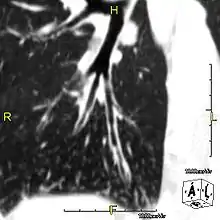

The main consequence of impaired ciliary function is reduced or absent mucus clearance from the lungs, and susceptibility to chronic recurrent respiratory infections, including sinusitis, bronchitis, pneumonia, and otitis media. Progressive damage to the respiratory system is common, including progressive bronchiectasis beginning in early childhood, and sinus disease (sometimes becoming severe in adults). However, diagnosis is often missed early in life despite the characteristic signs and symptoms.[1] In males, immotility of sperm can lead to infertility, although conception remains possible through the use of in vitro fertilization, there also are reported cases where sperm were able to move.[2] Trials have also shown that there is a marked reduction in fertility in female sufferers of Kartagener's syndrome due to dysfunction of the oviductal cilia.[3]

Many affected individuals experience hearing loss and show symptoms of otitis media which demonstrates variable responsiveness to the insertion of myringotomy tubes or grommets. Some patients have a poor sense of smell, which is believed to accompany high mucus production in the sinuses (although others report normal – or even acute – sensitivity to smell and taste). Clinical progression of the disease is variable, with lung transplantation required in severe cases. Susceptibility to infections can be drastically reduced by an early diagnosis. Treatment with various chest physiotherapy techniques has been observed to reduce the incidence of lung infection and to slow the progression of bronchiectasis dramatically. Aggressive treatment of sinus disease beginning at an early age is believed to slow long-term sinus damage (although this has not yet been adequately documented). Aggressive measures to enhance clearance of mucus, prevent respiratory infections, and treat bacterial superinfections have been observed to slow lung-disease progression. Although the true incidence of the disease is unknown, it is estimated to be 1 in 32,000,[4] although the actual incidence may be as high as 1 in 15,000.

When accompanied by the combination of situs inversus (reversal of the internal organs), chronic sinusitis, and bronchiectasis, it is known as Kartagener syndrome (only 50% of primary ciliary dyskinesia cases include situs inversus).